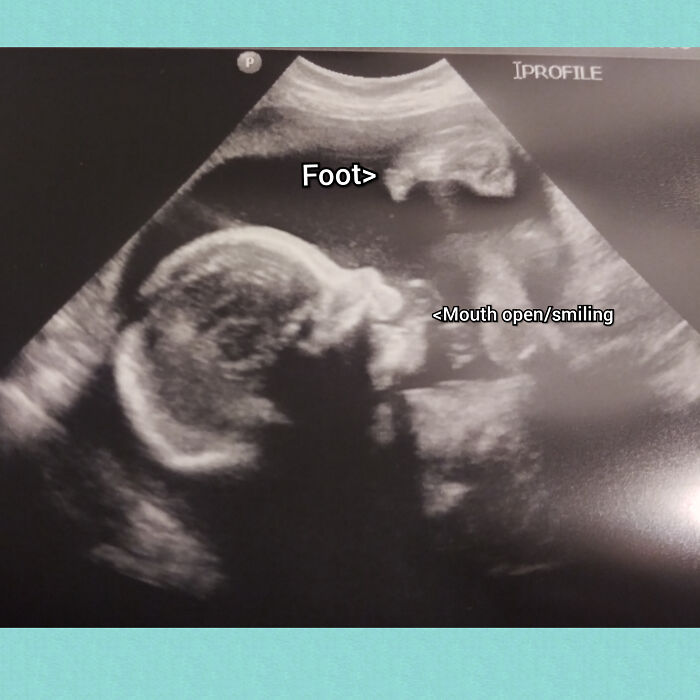

47. Finally Pregnant After Infertility Treatment!

Kitchen-Big-677

The ‘mom’ reply: